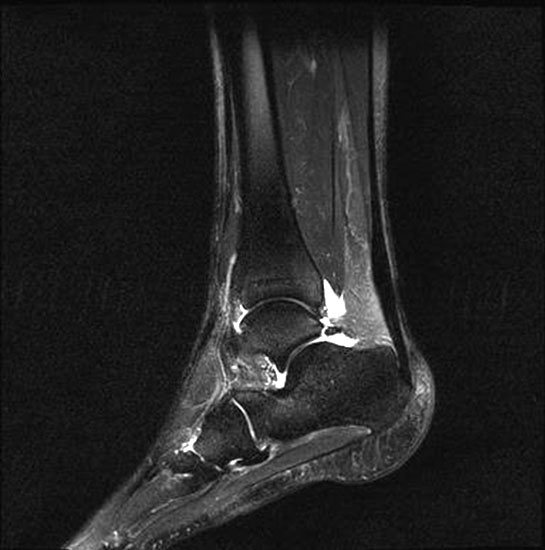

Stoßwellentherapie bei osteochondralen Läsionen

Die Osteochondrosis dissecans tali (OD) ist definiert als lokalisierte Pathologie der Gelenkfläche des Talus, die zur Abtrennung eines kartilaginären Fragmentes und subchondralen Knochens führen kann 93. Es existieren am Körper 3 Prädilektionsstellen für die Entwicklung einer OD mit unterschiedlicher Häufigkeit: Femurkondylen 75%, Talus 12% und Capitulum humeri 12%, sowie sonstigen Lokalisationen 1%. Abhängig vom Zeitpunkt des Auftretens unterscheidet man die juvenile Form (offene Wachstumsfuge) von der adulten Form (geschlossene Wachstumsfuge) (Dotti 2002).

Nach Dotti sind am Talus vorrangig die posteromediale und die anterolaterale Talusschulter betroffen. Die Ätiologie der OD an der anterolateralen Talusschulter scheint vermehrt traumatisch/repetitiv mikrotraumatisch zu sein, die der posteromedialen Talusschulter vermehrt idiopathisch.

Die Stadieneinteilung nach Berndt und Harty umfasst 4 Stadien und ist unabhängig von der Lokalisation der OD anwendbar 94.

Die Stadieneinteilung nach ARCO (Association Internationale de Recherche sur la Circulation Osseuse) berücksichtigt die Kombination aus MRI-Zeichen, Nativradiologie und Knochenszintigraphie 95.

Als Alternative zu operativen Maßnahmen wird bei frühen Stadien der OD auch der Einsatz fokussierter Stoßwellentherapie diskutiert, wenngleich es bislang wenig klinische Studien zur ESWT bei OD am Talus gibt.

Die ESWT wird in der Regel in einer Sitzung unter Leitungs– oder Allgemeinanästhesie durchgeführt, wobei nach Empfehlungen der DIGEST eine mittlere Energieflussdichte von 0,35mJ/mm² und eine Anzahl von 2500 Impulsen empfohlen wird. Bei hochenergetischer Behandlung (>0,5mJ/mm²) kann eine Schädigung des Knorpels nicht sicher ausgeschlossen werden 97.

Nach der Behandlung wird eine Entlastung für ca. 2 - 6 Wochen empfohlen. MRT-Kontrollen sind nach 3, 6 und 12 Monaten sinnvoll.

Aufgrund der Datenlage kann die Anwendung der ESWT bei osteochondralen Läsionen des Talus in frühen Stadien (1 und 2 nach ARCO) erwogen werden. Für eine Therapieempfehlung sind allerdings weitere Studien, insbesondere zur Therapie der OD des Talus zwingend erforderlich. Aufgrund der technischen Schwierigkeit der Behandlung bei teilweise schlechter Erreichbarkeit der Läsion, sollte diese Indikation erfahrenen Anwendern vorbehalten bleiben.